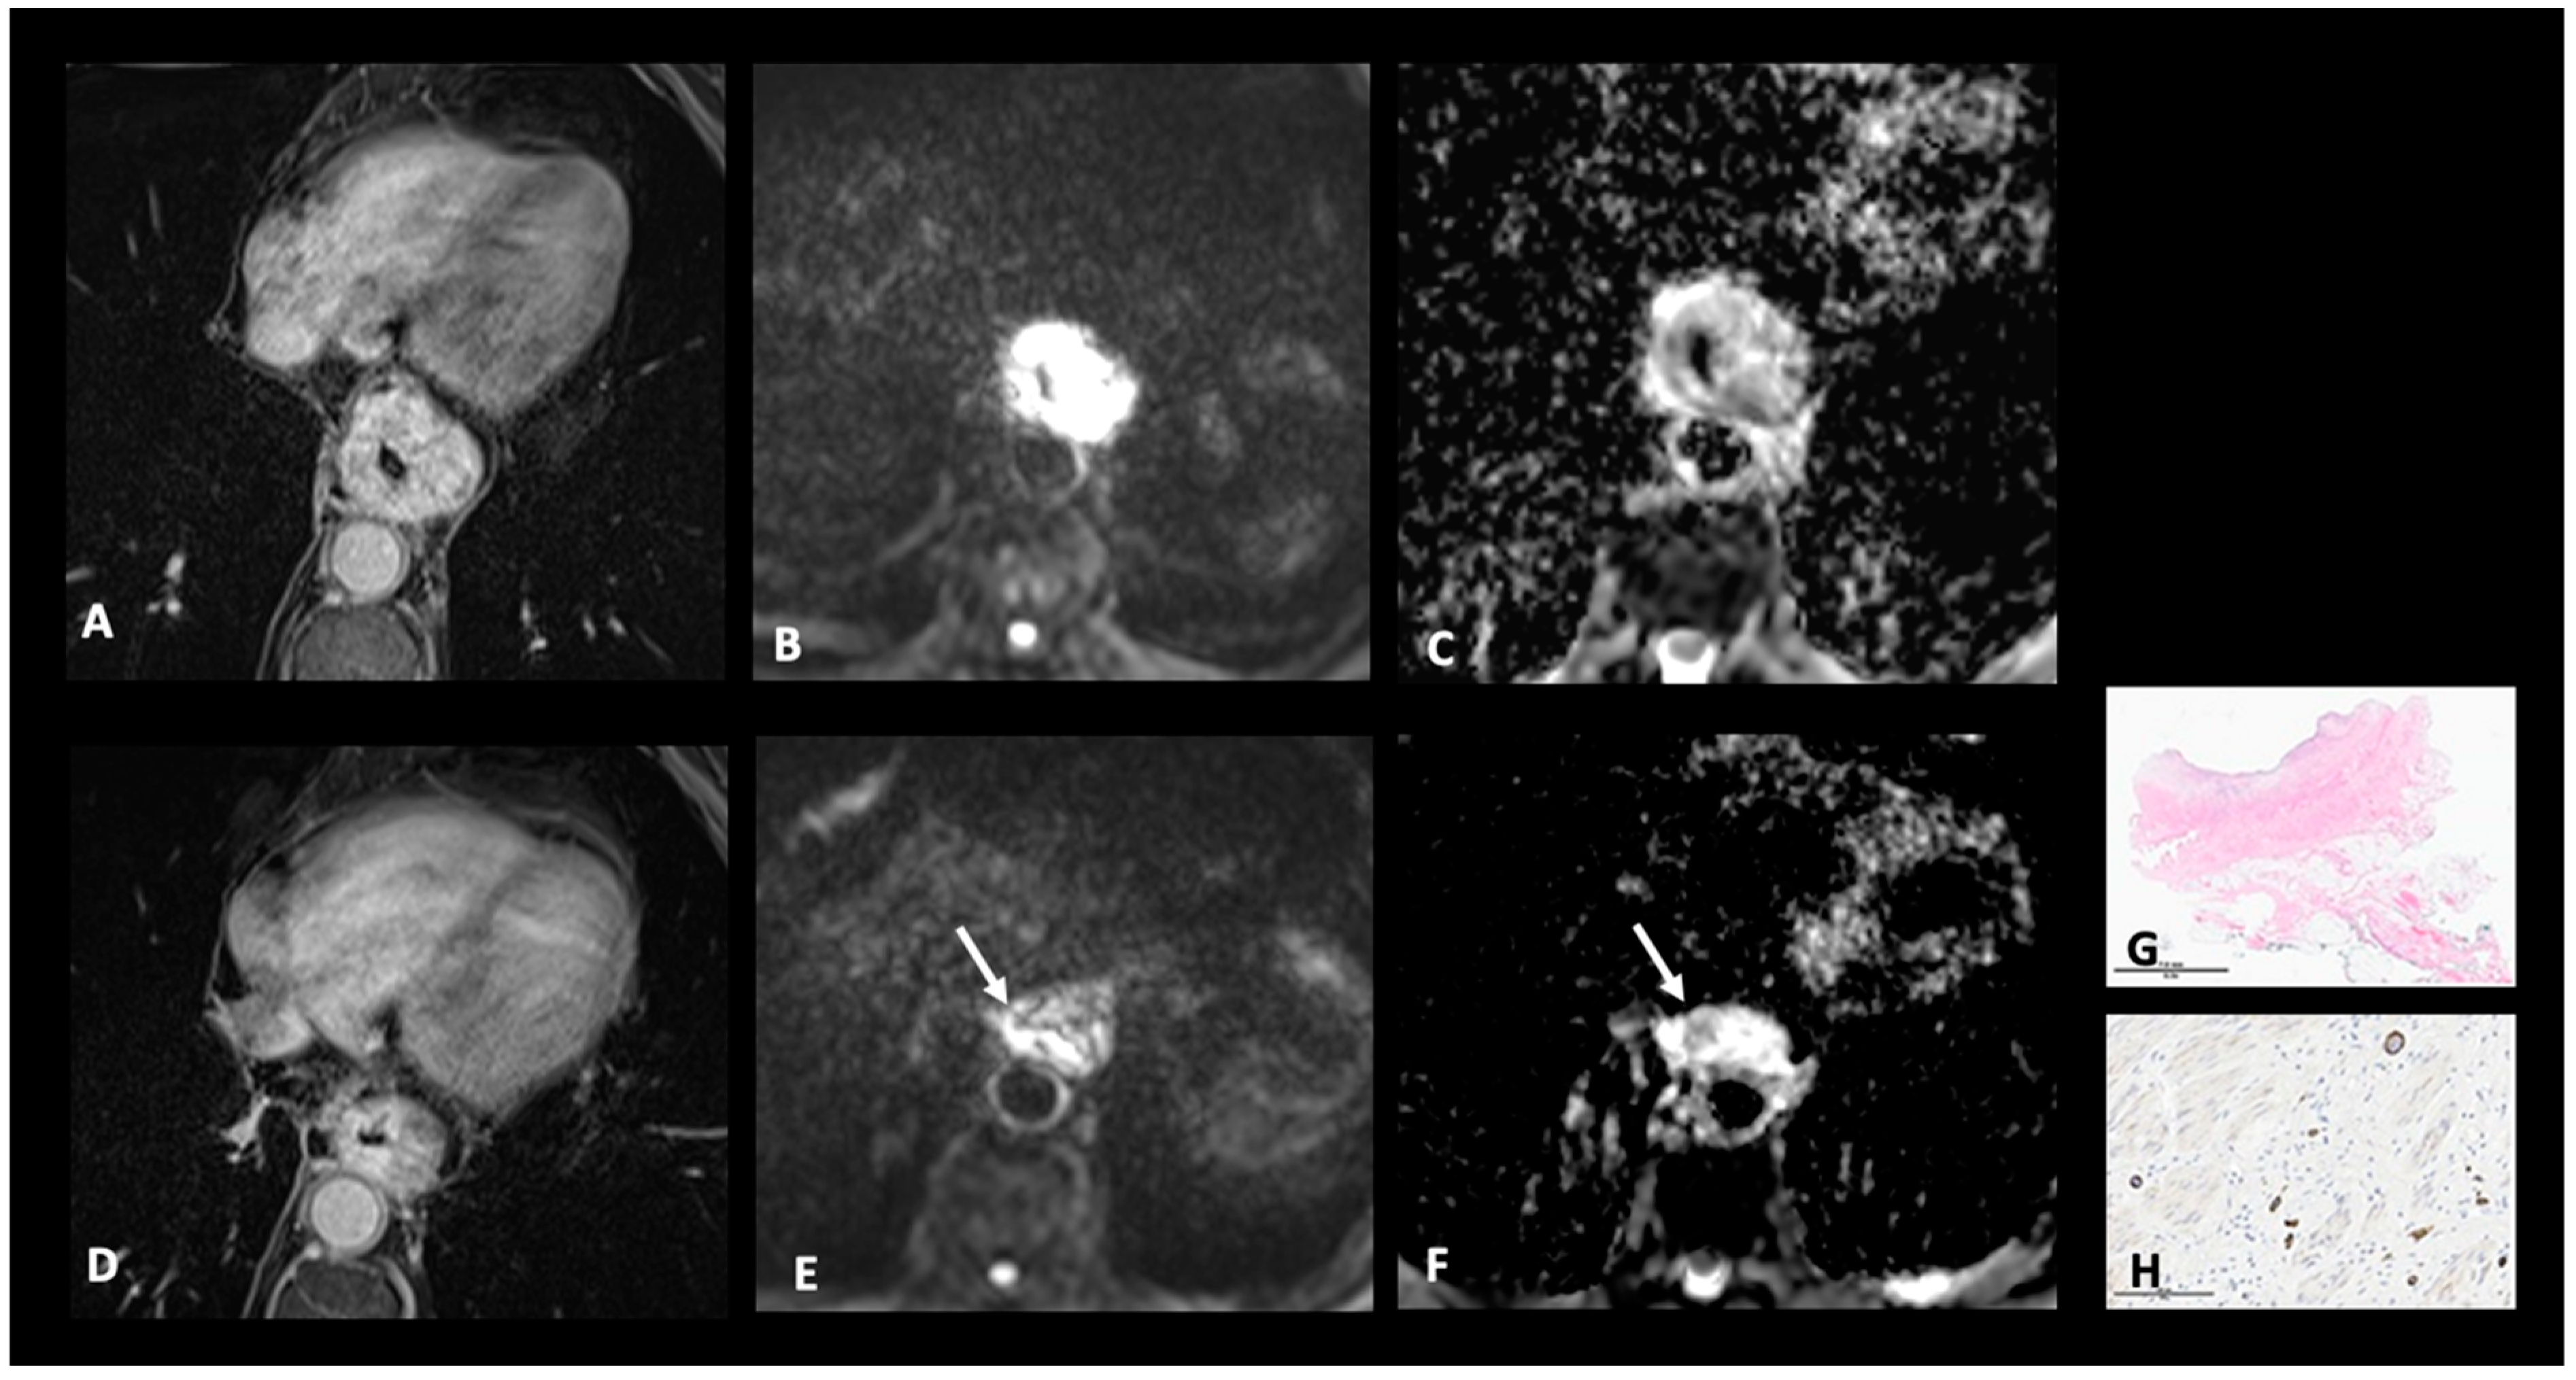

4.1. T Restaging

- Chapellier, P.; Fasquelle, F.; Saglietti, C.; Kinj, R.; Mantziari, S.; Schäfer, M.; Haefliger, L.; Jreige, M.; Vietti Violi, N.; Sempoux, C.; et al. Prospective Evaluation of MR-TRG (Tumor Regression Grade) in Esophageal Cancer after Neo-Adjuvant Therapy: Preliminary Results. Eur. J. Radiol. 2024, 171, 111263. [Google Scholar] [CrossRef]